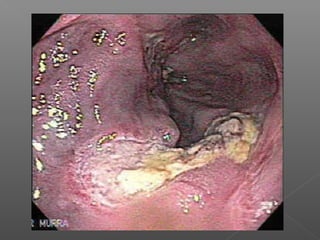

 Síndrome de Mallory-Weis: ulceraciones de la

unión gastroesofágica 5-15%

› Cesa espontáneamente 90%

› Electrocoagulación bipolar

Ulceras pépticas

 50% causa de sangrado

Factores de predisposición

 Ácido

 H pylori: 71% a 90% úlceras duodenales

 Ingesta de AINES:

› Mayores de 65 años

› Historia de úlcera péptica